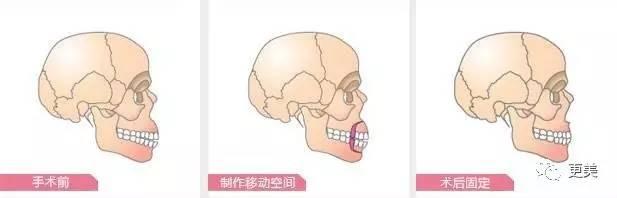

骨性的就要做正颌手术了,上面提到过单纯戴牙套是不能改善嘴凸问题,并且因为骨性影响,即使将牙性部分问题解决,也很容易复发,所以想要改善就必须进行手术

将发育过度的上下颌骨截掉一部分,再固定缝合。特别要注意:正颌手术是危险范畴的手术,必须去三级整形医院或者三级综合医院的整形外科!

确定了是骨性问题,还需要知道自己的问题出在哪,是上颌前突畸形

还是双颌前突畸形

两种问题,都会有开唇露齿,自然状态下双唇不能闭合,微笑时牙龈外露过多的表现

如果强迫闭嘴的话,唇部与颏部之间有明显的软组织隆起